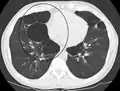

Outros exames

A realização de uma radiografia ao tórax e de um hemograma permitem excluir outras condições no momento do diagnóstico.[69] Os sinais característicos da DPOC observáveis em radiografia são pulmões sobre-expandidos, diafragma achatado e espaço retroesternal aumentado. Ao mesmo tempo, a radiografia permite excluir outras doenças pulmonares, como pneumonia, edema pulmonar ou pneumotórax.[70] Uma tomografia axial computorizada ao tórax permite mostrar a distribuição do enfisema pelos pulmões e pode ajudar a excluir outras doenças pulmonares.[18] No entanto, a não ser nos casos em que se planeie a realização de uma cirurgia, esta distribuição raramente influencia o tratamento.[18] Pode ainda ser realizada uma gasometria arterial para determinar a necessidade de oxigénio suplementar. Este exame é recomendado em pessoas com VEF1 inferior a 35% do previsto, com saturação periférica de oxigénio inferior a 92% e pessoas com sintomas de insuficiência cardíaca congestiva.[17] Em regiões do mundo onde é comum a deficiência de alfa-1 antitripsina, as pessoas com DPOC devem considerar a realização deste exame, sobretudo aquelas com idade inferior a 45 anos e em que o enfisema afeta a parte inferior dos pulmões.[17]